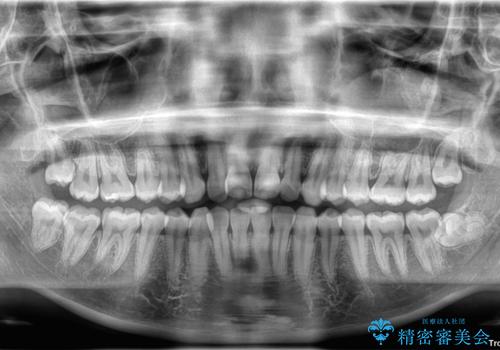

治療終了時

前歯が自然なアーチにきれいに並び、正中(上下の中心線)も整い、咬み合わせも良好です。

側方拡大することで、非抜歯であるにも関わらず前歯が前方に出ることなく、バランスの良い仕上がりとなりました。